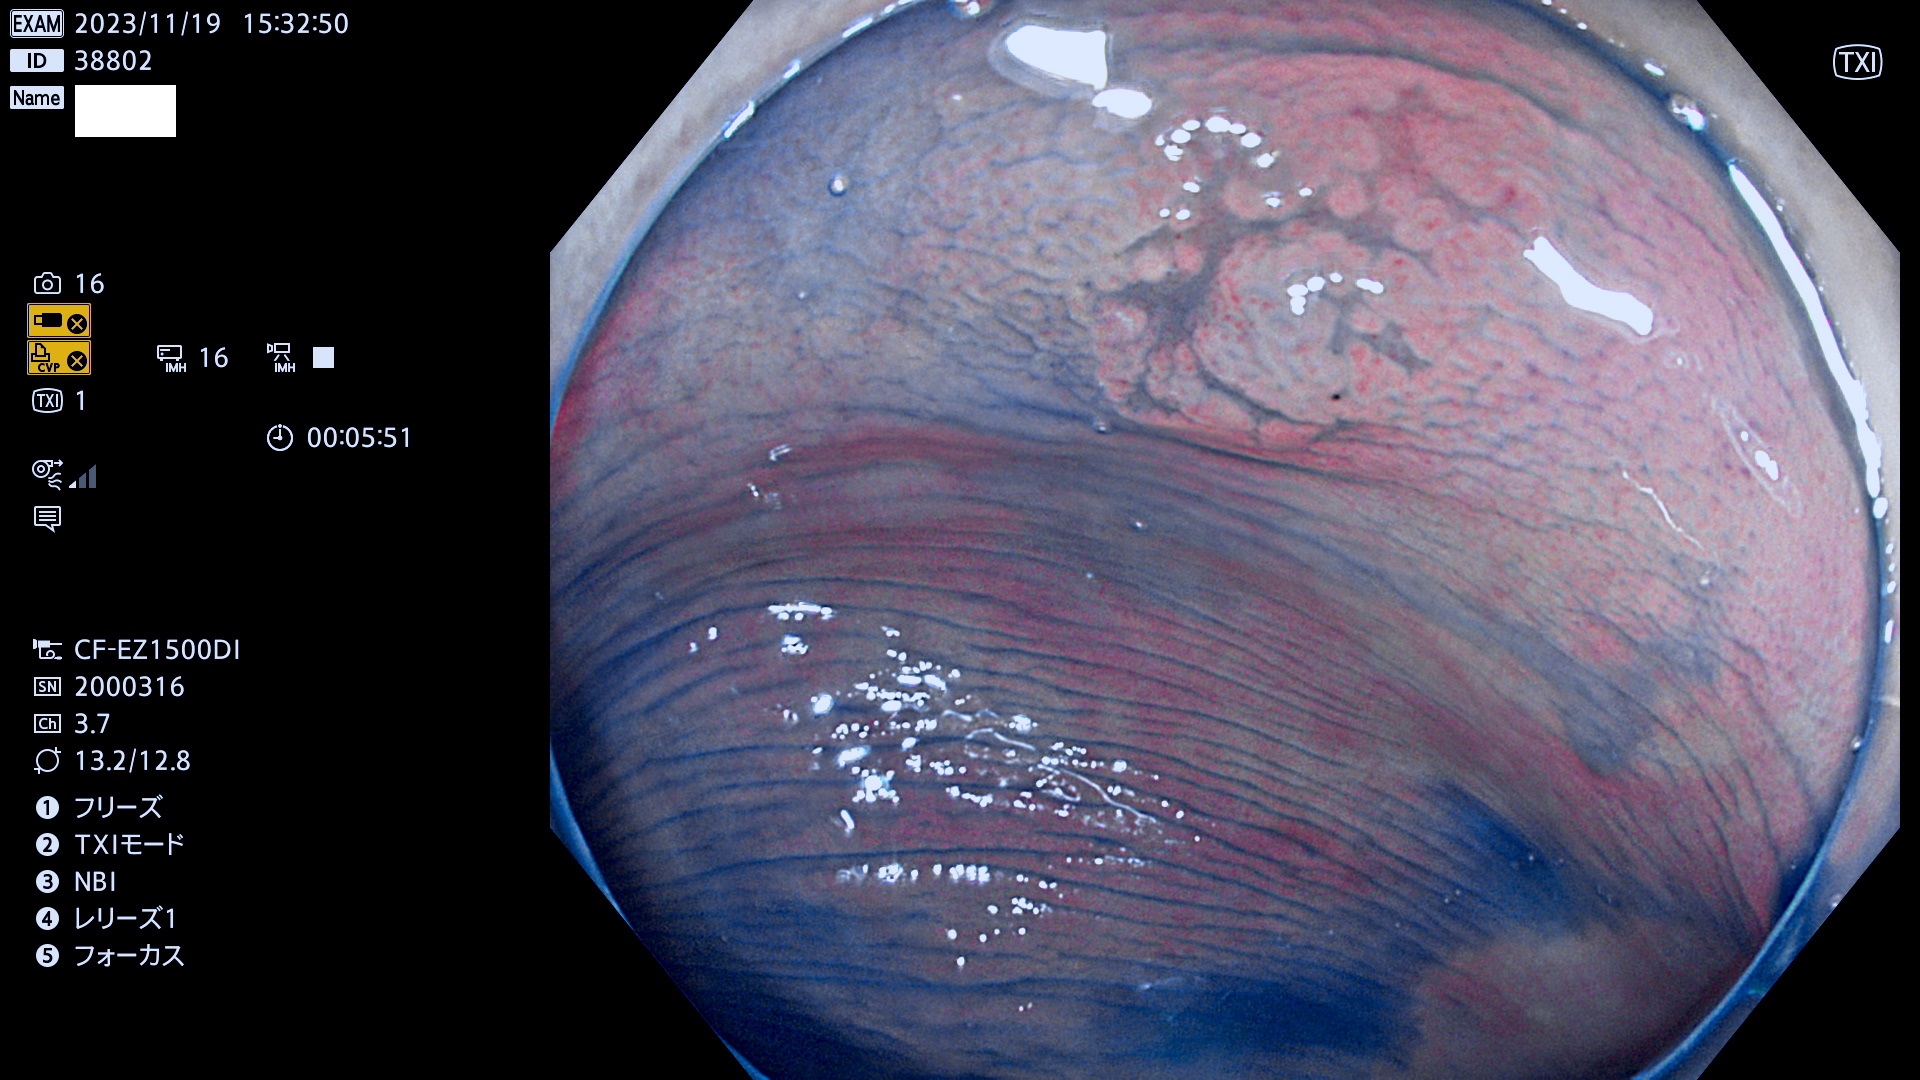

表面型腺腫(Flat Adenoma)の中で、完全に平坦な物をUb、陥凹している物をUcと呼びます。平坦隆起型(Ua)よりも、発見が難しく危険な病変です。このタイプは「内視鏡後・大腸癌の重要犯人」であり、この発見率は「腺腫発見率」よりも、重要な意味があります。

専門的)何故、陥凹していると危険? 癌遺伝子の変異が蓄積すると細胞分裂が盛んになり隆起するのでは?と通常は思われるでしょう。しかし実際は逆です。これは2022年の記事にある「細胞はストレスに直面したら細胞分裂を止める(細胞老化に入り休眠する)という生命の基本的現象」によるものです(Oncogene Stress)。細胞老化を起こすのが癌抑制遺伝子で、この安全装置(ブレーキ)が壊れると癌になります(休眠からの覚醒)。ですから陥凹は「まだ癌では無いが癌化の直前」を意味します。特に「小サイズなのに陥凹している」病変は短期間に腫瘍進化(⇒2021年記事)が起きたことを意味します(=ゲノム不安定性

専門的)Uc=De Novo癌? 内視鏡の解像度が低かった時代、このような説もありました。しかし今日の高精度内視鏡では良性の微小なUc型腺腫が日常的に見つかります。私見ですが「Ucこそが多段階発癌(Adenoma-Carcinoma Sequence)のMain Route」と考えます。

毎週の検査(木・金・土・日)に発見されたUb、Uc型・腺腫を、その週の日曜の夜にUPし1週間、提示します。

抽出の対象期間 2023年11月16日(木)〜11月20(日)の5日間(60件の検査)11件